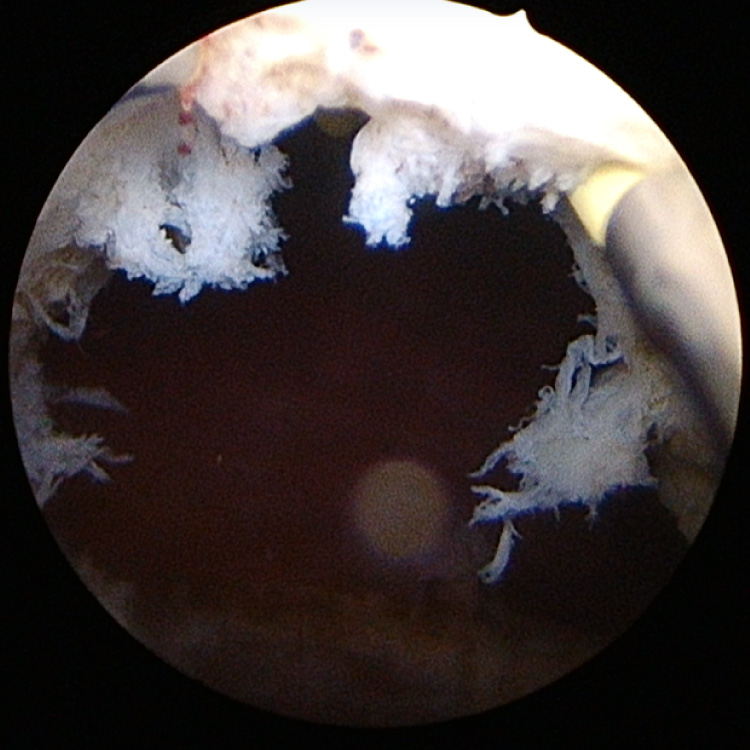

HoLEP

ホルミウムレーザーによる腺腫の核出(内腺のくり抜き)

腺腫の核出後